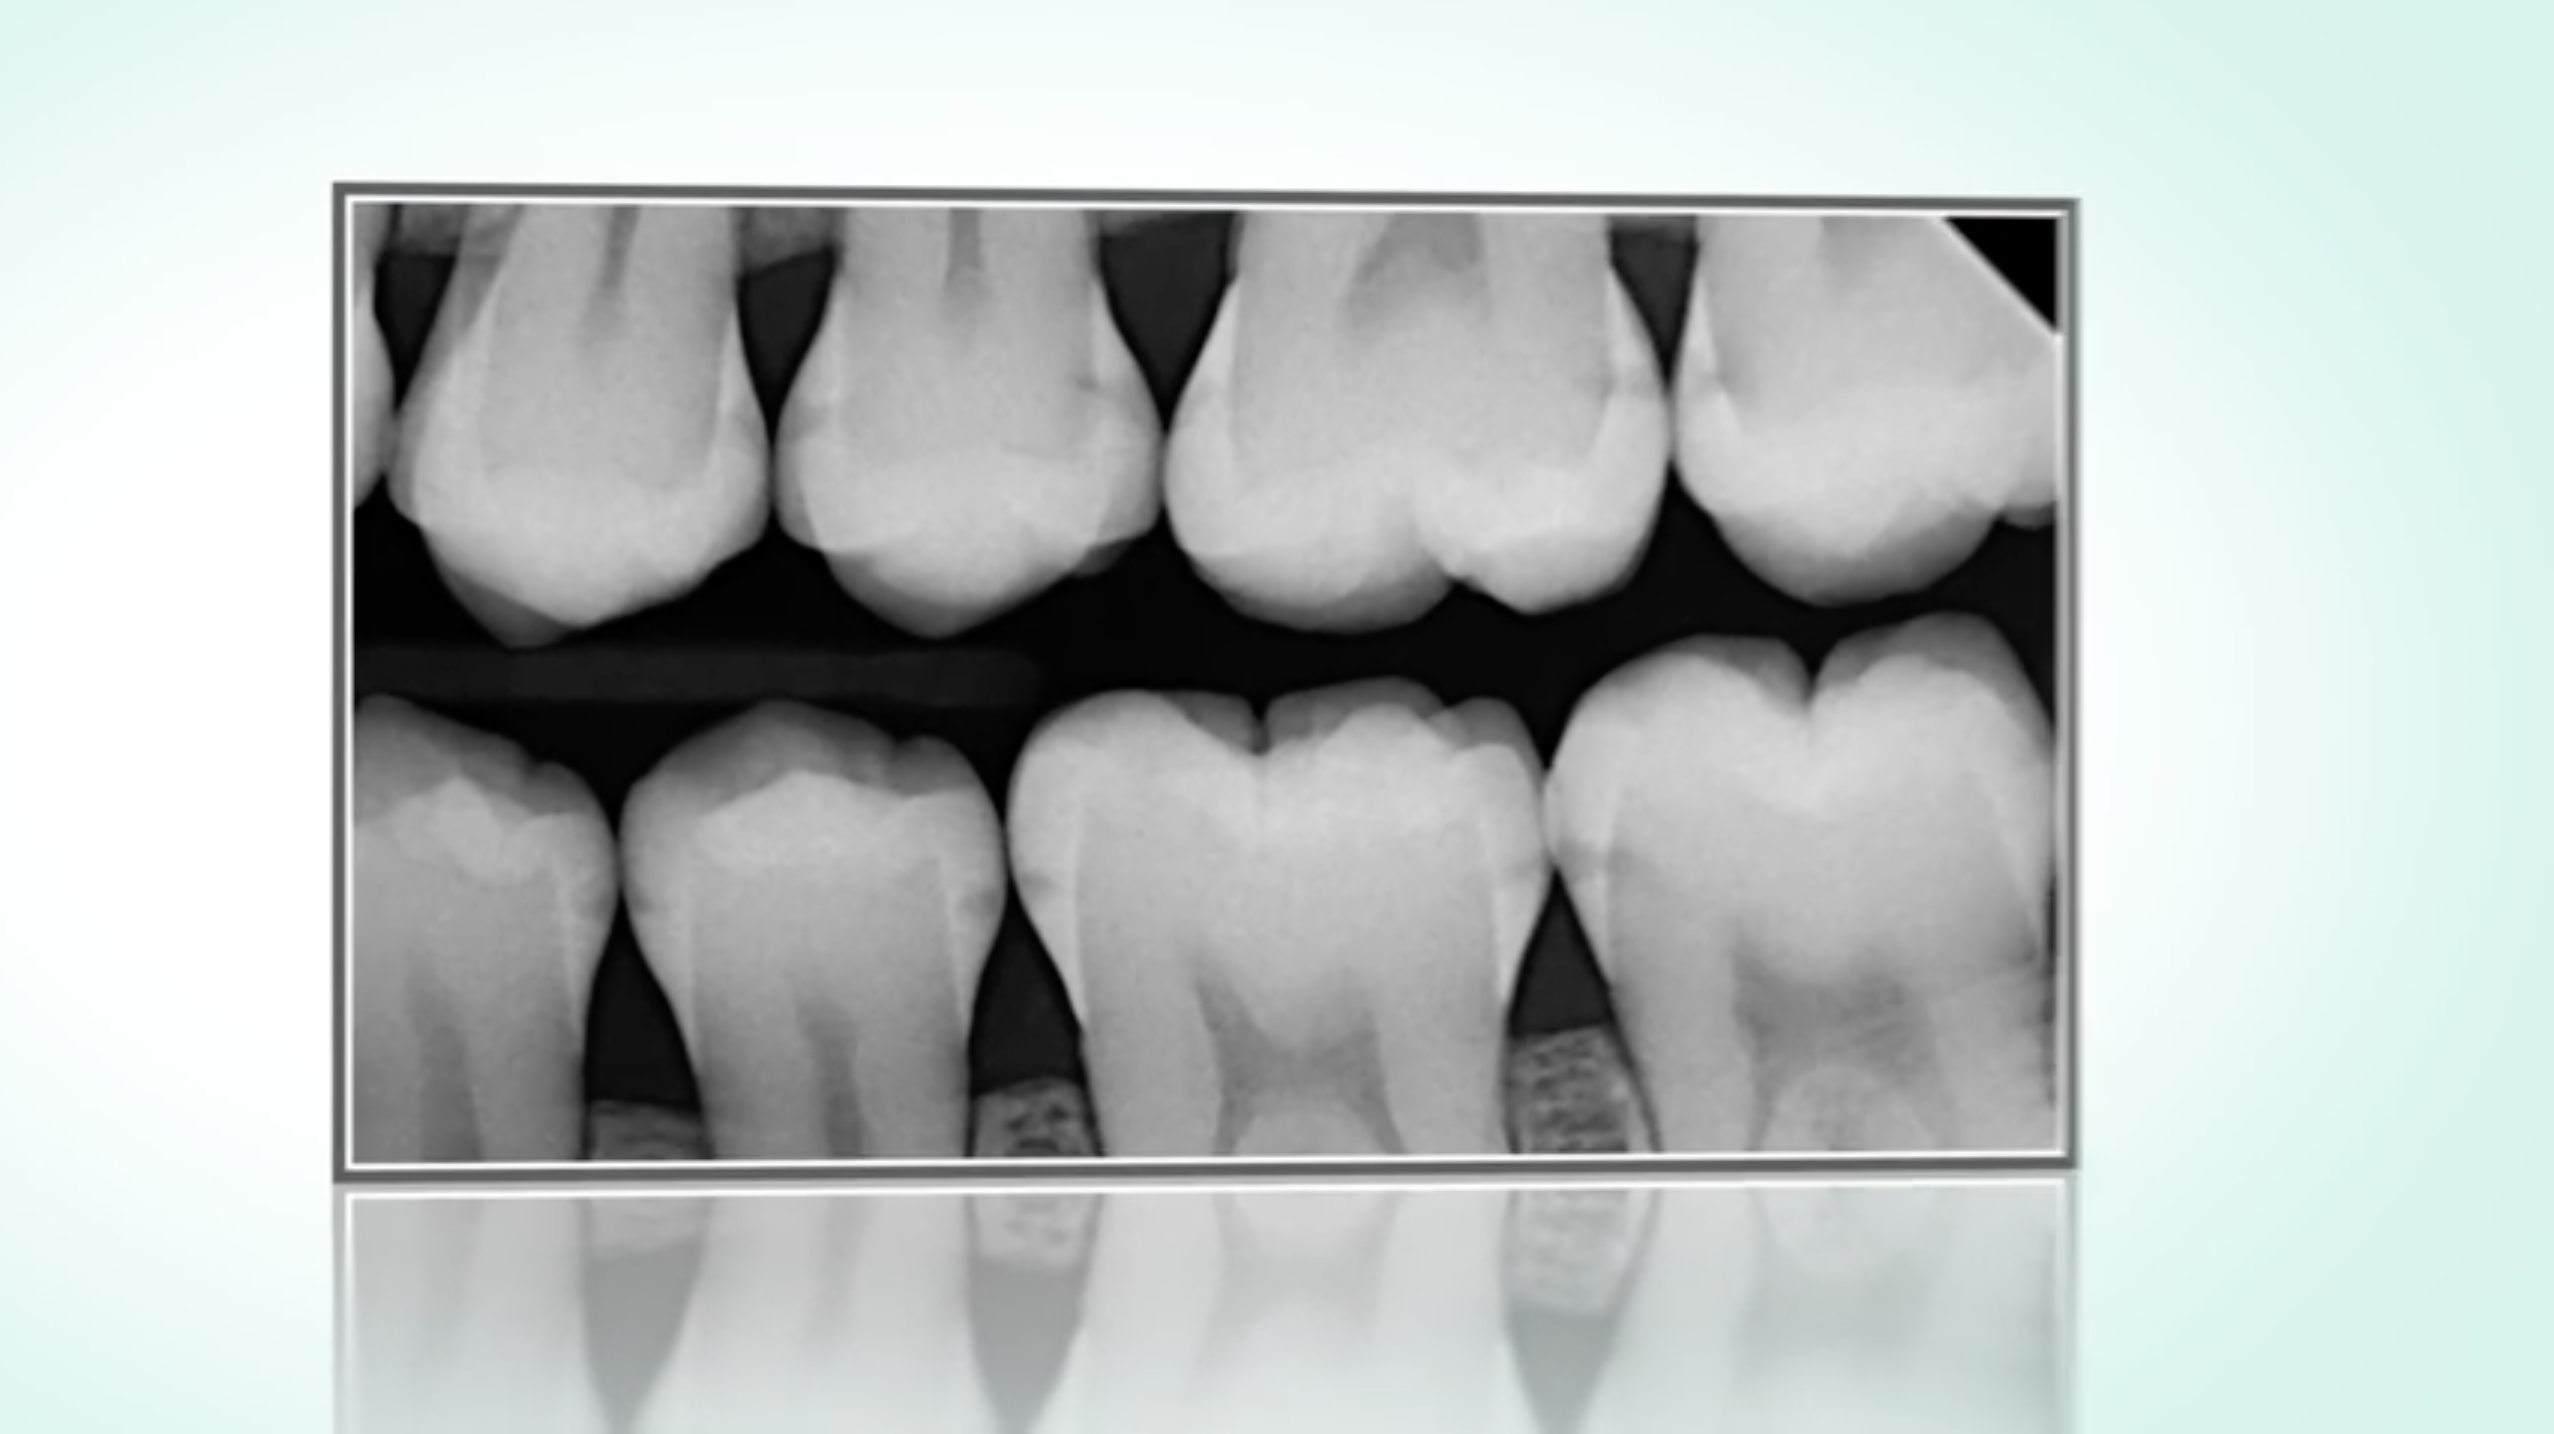

The so-called caries infiltration offers a completely new possibility to stop incipient caries early in just one session - without drilling and without sacrificing healthy tooth substance.

However, this is only possible for very small, incipient lesions.

The "infiltrant", a highly fluid plastic, penetrates into the porous enamel caries and seals the diffusion paths for cariogenic acids. Thus, the caries can be stopped early, in the interdental space as well as on smooth surfaces.

What to do when caries starts in the interdental space?